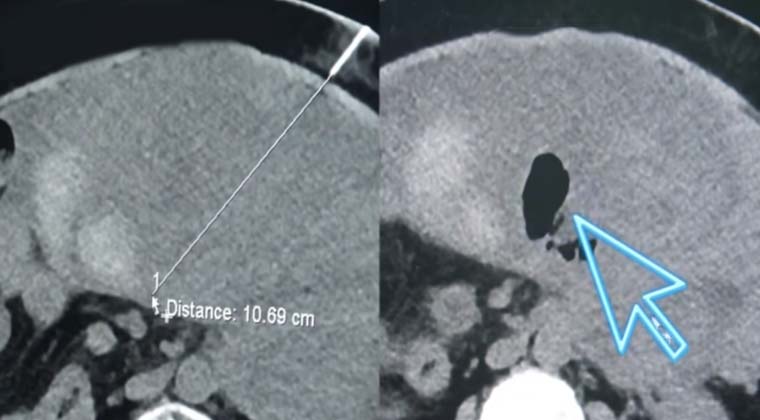

Типичный клинический случай

До абляции

После абляции